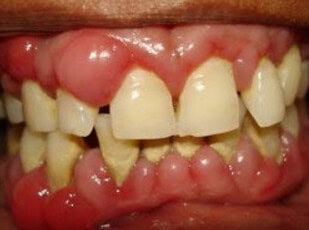

Most people understand that poor dental hygiene leads to cavities and gum disease, but groundbreaking research reveals a far more serious consequence: it could be silently threatening your heart. A remarkable 17-year study following older adults found that those with periodontitis faced a 50% higher risk of developing ischemic heart disease, with women showing an even more alarming 110% increased risk. Even more striking, recent research shows that seniors with no remaining teeth have an 83% higher risk of dying from cardiovascular disease compared to those who’ve maintained at least 20 teeth. This isn’t just about statistics—it’s about a hidden health crisis affecting millions of older adults. As we age, the stakes of dental neglect become literally a matter of life and death. The mouth, once thought to be separate from the rest of the body, is now recognized as a gateway that can either protect or endanger our cardiovascular system.